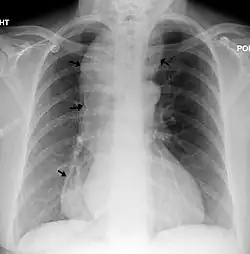

A chest X-ray showing achalasia (arrows point to the outline of the massively dilated esophagus)

Due to the similarity of symptoms, achalasia can be mistaken for more common disorders such as gastroesophageal reflux disease (GERD), hiatus hernia, and even psychosomatic disorders. Specific tests for achalasia are barium swallow and esophageal manometry. In addition, endoscopy of the esophagus, stomach, and duodenum (esophagogastroduodenoscopy or EGD), with or without endoscopic ultrasound, is typically performed to rule out the possibility of cancer.[11] The internal tissue of the esophagus generally appears normal in endoscopy, although a "pop" may be observed as the scope is passed through the non-relaxing lower esophageal sphincter with some difficulty, and food debris may be found above the LES.